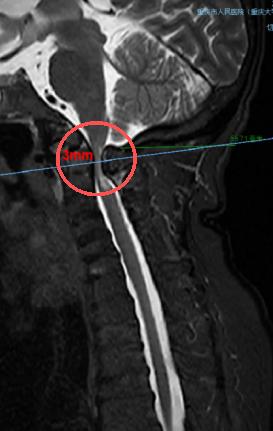

術前,頸椎CT顯示寰樞椎脫位(正常為寰椎、樞椎在同一水平線)。重慶市人民醫院(重慶大學附屬人民醫院)供圖